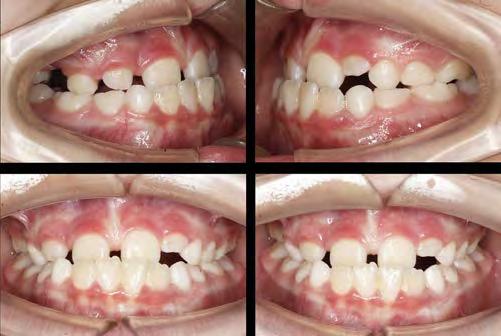

Ortodoncia interdisciplinar, un enfoque colaborativo para el tratamiento integral de maloclusiones

Es un hecho que la práctica de tratamientos de Ortodoncia interdisciplinar ha aumentado en los últimos años. Esto se debe a una combinación de avances en la tecnología y técnicas de tratamiento, a una mayor conciencia sobre la importancia de una salud oral integral, a una mayor demanda de tratamientos estéticos y a una mayor disponibilidad de tratamientos de Ortodoncia. Todo ello hace que la Ortodoncia interdisciplinar tenga hoy en día mayor relevancia que nunca y esto es algo que podremos comprobar en una de las citas científicas del año: el 69 Congreso que la Sociedad Española de Ortodoncia (SEDO) celebrará, entre el 7 y 10 de junio en Bilbao, y cuyo tema principal será «Ortodoncia interdisciplinar. La llave del éxito en el tratamiento del paciente adulto».

Los avances en la tecnología y las técnicas de tratamiento están permitiendo a los especialistas en Ortodoncia abordar problemas más complejos y tratarlos de manera más efectiva. Estos avances han facilitado la colaboración entre diferentes especialistas, lo que ha impulsado el desarrollo de la Ortodoncia interdisciplinar. Al mismo tiempo, llevamos años notando una

mayor demanda de tratamientos estéticos, de pacientes que están buscando tratamientos de ortodoncia que no solo mejoren su salud oral, sino también su apariencia. Todo ello junto a una mayor disponibilidad de tratamientos de ortodoncia, hace que sea muy común que los pacientes busquen tratamientos más especializados y personalizados que aborden todas sus necesidades específicas. Y, para dar respuesta a todo ello, el

trabajo del ortodoncista con otros especialistas es imprescindible.

Para el Dr. Eduardo Espinar Escalona, médico estomatólogo y ortodoncista, «en la actualidad, la tendencia es el manejo multidisciplinar. Son muchas las disciplinas, cada vez más complejas, que necesitan la intervención de diferentes profesionales. Creo que casi todos los pacientes adultos, y en ocasiones en crecimiento, necesitan una planificación multidisciplinar. Puesto que actualmente la mayoría de los tratamientos de nuestras consultas son pacientes adultos, eso es sinónimo de necesidades de abordaje interdisciplinar».